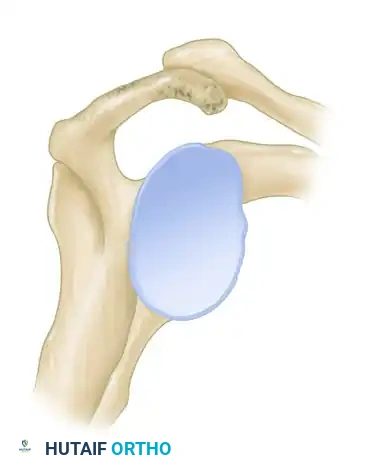

Figure 46-4 (Type I): A flat acromion with minimal compromise of the supraspinatus outlet. Associated with the lowest risk of rotator cuff pathology.